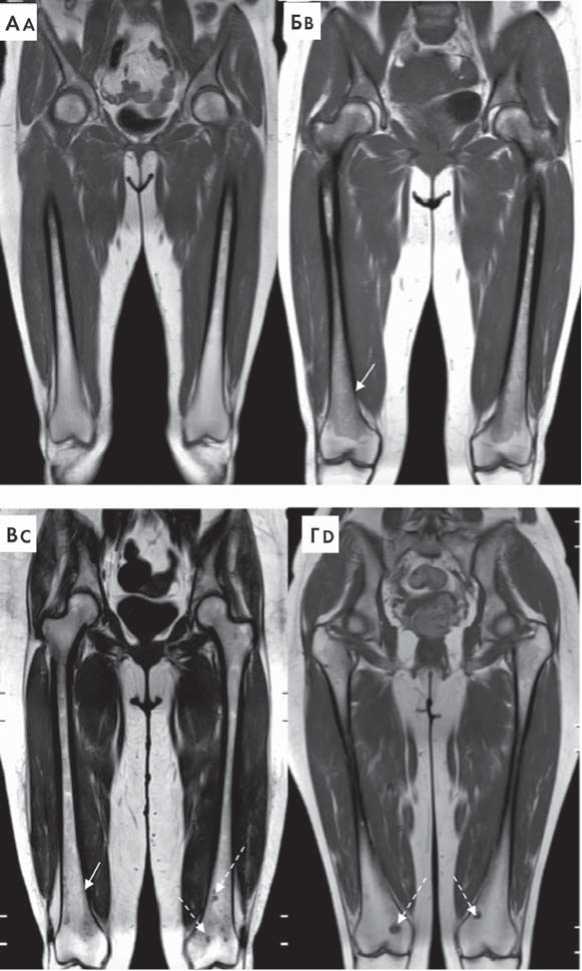

Основными преимуществами низкодозовой КТ скелета и ПЭТ-КТ являются высокое разрешение визуализации кортикальной и трабекулярной части кости, относительно быстрое время исследования, возможность 3D-реконструкций изображений [4]. Однако в данных методах исследования используется ионизирующее излучение, что может быть ограничением для некоторой категории больных.

Рисунок 1. Типы поражения костного мозга при ММ на примере бедренных костей в режиме Т1-ВИ. А — нормальный костный мозг, Б — диффузный тип поражения костного мозга (указан сплошной стрелкой), В — диффузно-очаговый тип поражения костного мозга (диффузная инфильтрация указана сплошной стрелкой, очаги поражения указаны прерывистой стрелкой), Г — очаговый тип инфильтрации костного мозга (очаги поражения указаны прерывистой стрелкой)

Figure 1. Bone marrow infiltration patterns in MM patients, femur, T1WI. A — intact bone marrow, B — diffuse bone marrow infiltration (solid arrow), C — diffuse and focal infiltration (diffuse infiltration marked by solid arrow, foci — by dashed arrow), D — focal infiltration (dashed arrow)Определение типа инфильтрации костного мозга имеет важное прогностическое значение, так как магнитно-резонансная (МР) картина нормального, микронодулярного и очагового типов инфильтрации костного мозга обычно соответствует I и II стадиям заболевания по системе ISS, тогда как диффузный тип инфильтрации обычно встречается при III стадии заболевания по системе ISS [7]. По данным исследования R. Walker и соавт. [8], наличие 7 и более очагов инфильтрации костного мозга размером ≥ 5 мм по данным МРТ коррелирует с уменьшением общей выживаемости (ОВ) больных ММ. При отсутствии очагов инфильтрации костного мозга 5-летняя ОВ больных достигла 73 %, в то время как при наличии от 1 до 7 очагов или более 7 очагов инфильтрации костного мозга ОВ составляла 68 и 55 %, соответственно [7]. Таким образом, в 2014 г. Международная рабочая группа по изучению ММ определила наличие более одного очага инфильтрации костного мозга размером ≥ 5 мм, выявленных по данным МРТ, одним из признаков опухолевой активности, а также одним из диагностических критериев симптоматической ММ, требующей начала специфической терапии [2].